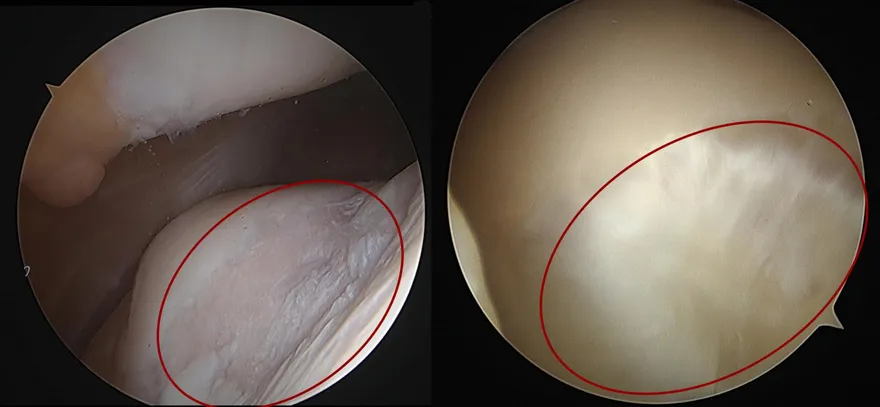

關節鏡手術

旋轉肌袖破裂

關節鏡軟骨再生促進手術

微創膝關節鏡手術

半月板損傷